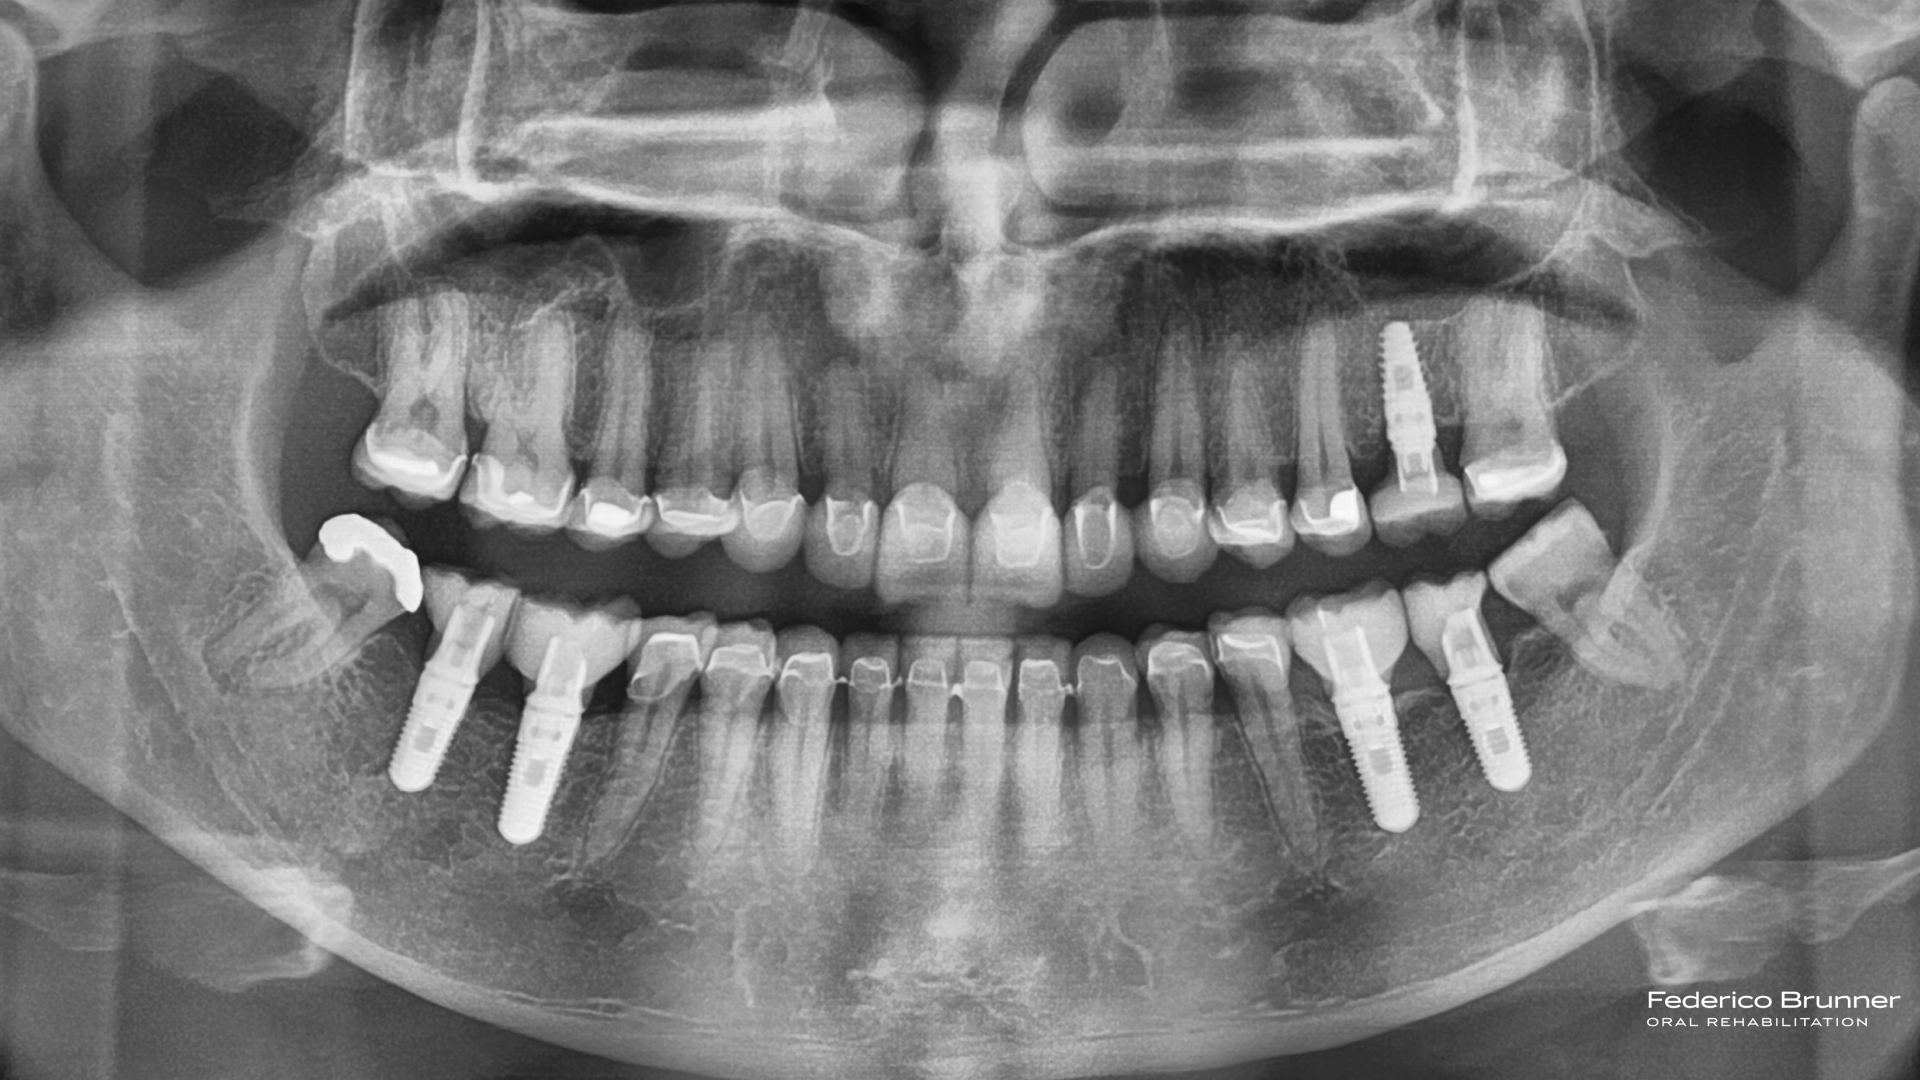

Alargamiento Coronario - Cirugia plástica de encías. Reposición piezas dentales perdidas con Implantes dentales Alargamiento coronario.-Coronas de porcelana Aumento de dimensión vertical. Ferula de descarga

La paciente quedó encantada con el "mock-up", lo que nos permitió comenzar el tratamiento. En este proceso, realizamos un alargamiento coronario para mejorar la sonrisa gingival, ya que exponía demasiada encía. Luego, planificamos y ejecutamos una rehabilitación total cerámica adherida sin metal. Además, reemplazamos las piezas perdidas con implantes dentales, lo que nos permitió restaurar la función y hacer desaparecer los problemas masticatorios y digestivos.

La paciente duerme todas las noches con su férula de descarga tipo Michigan para proteger la restauración